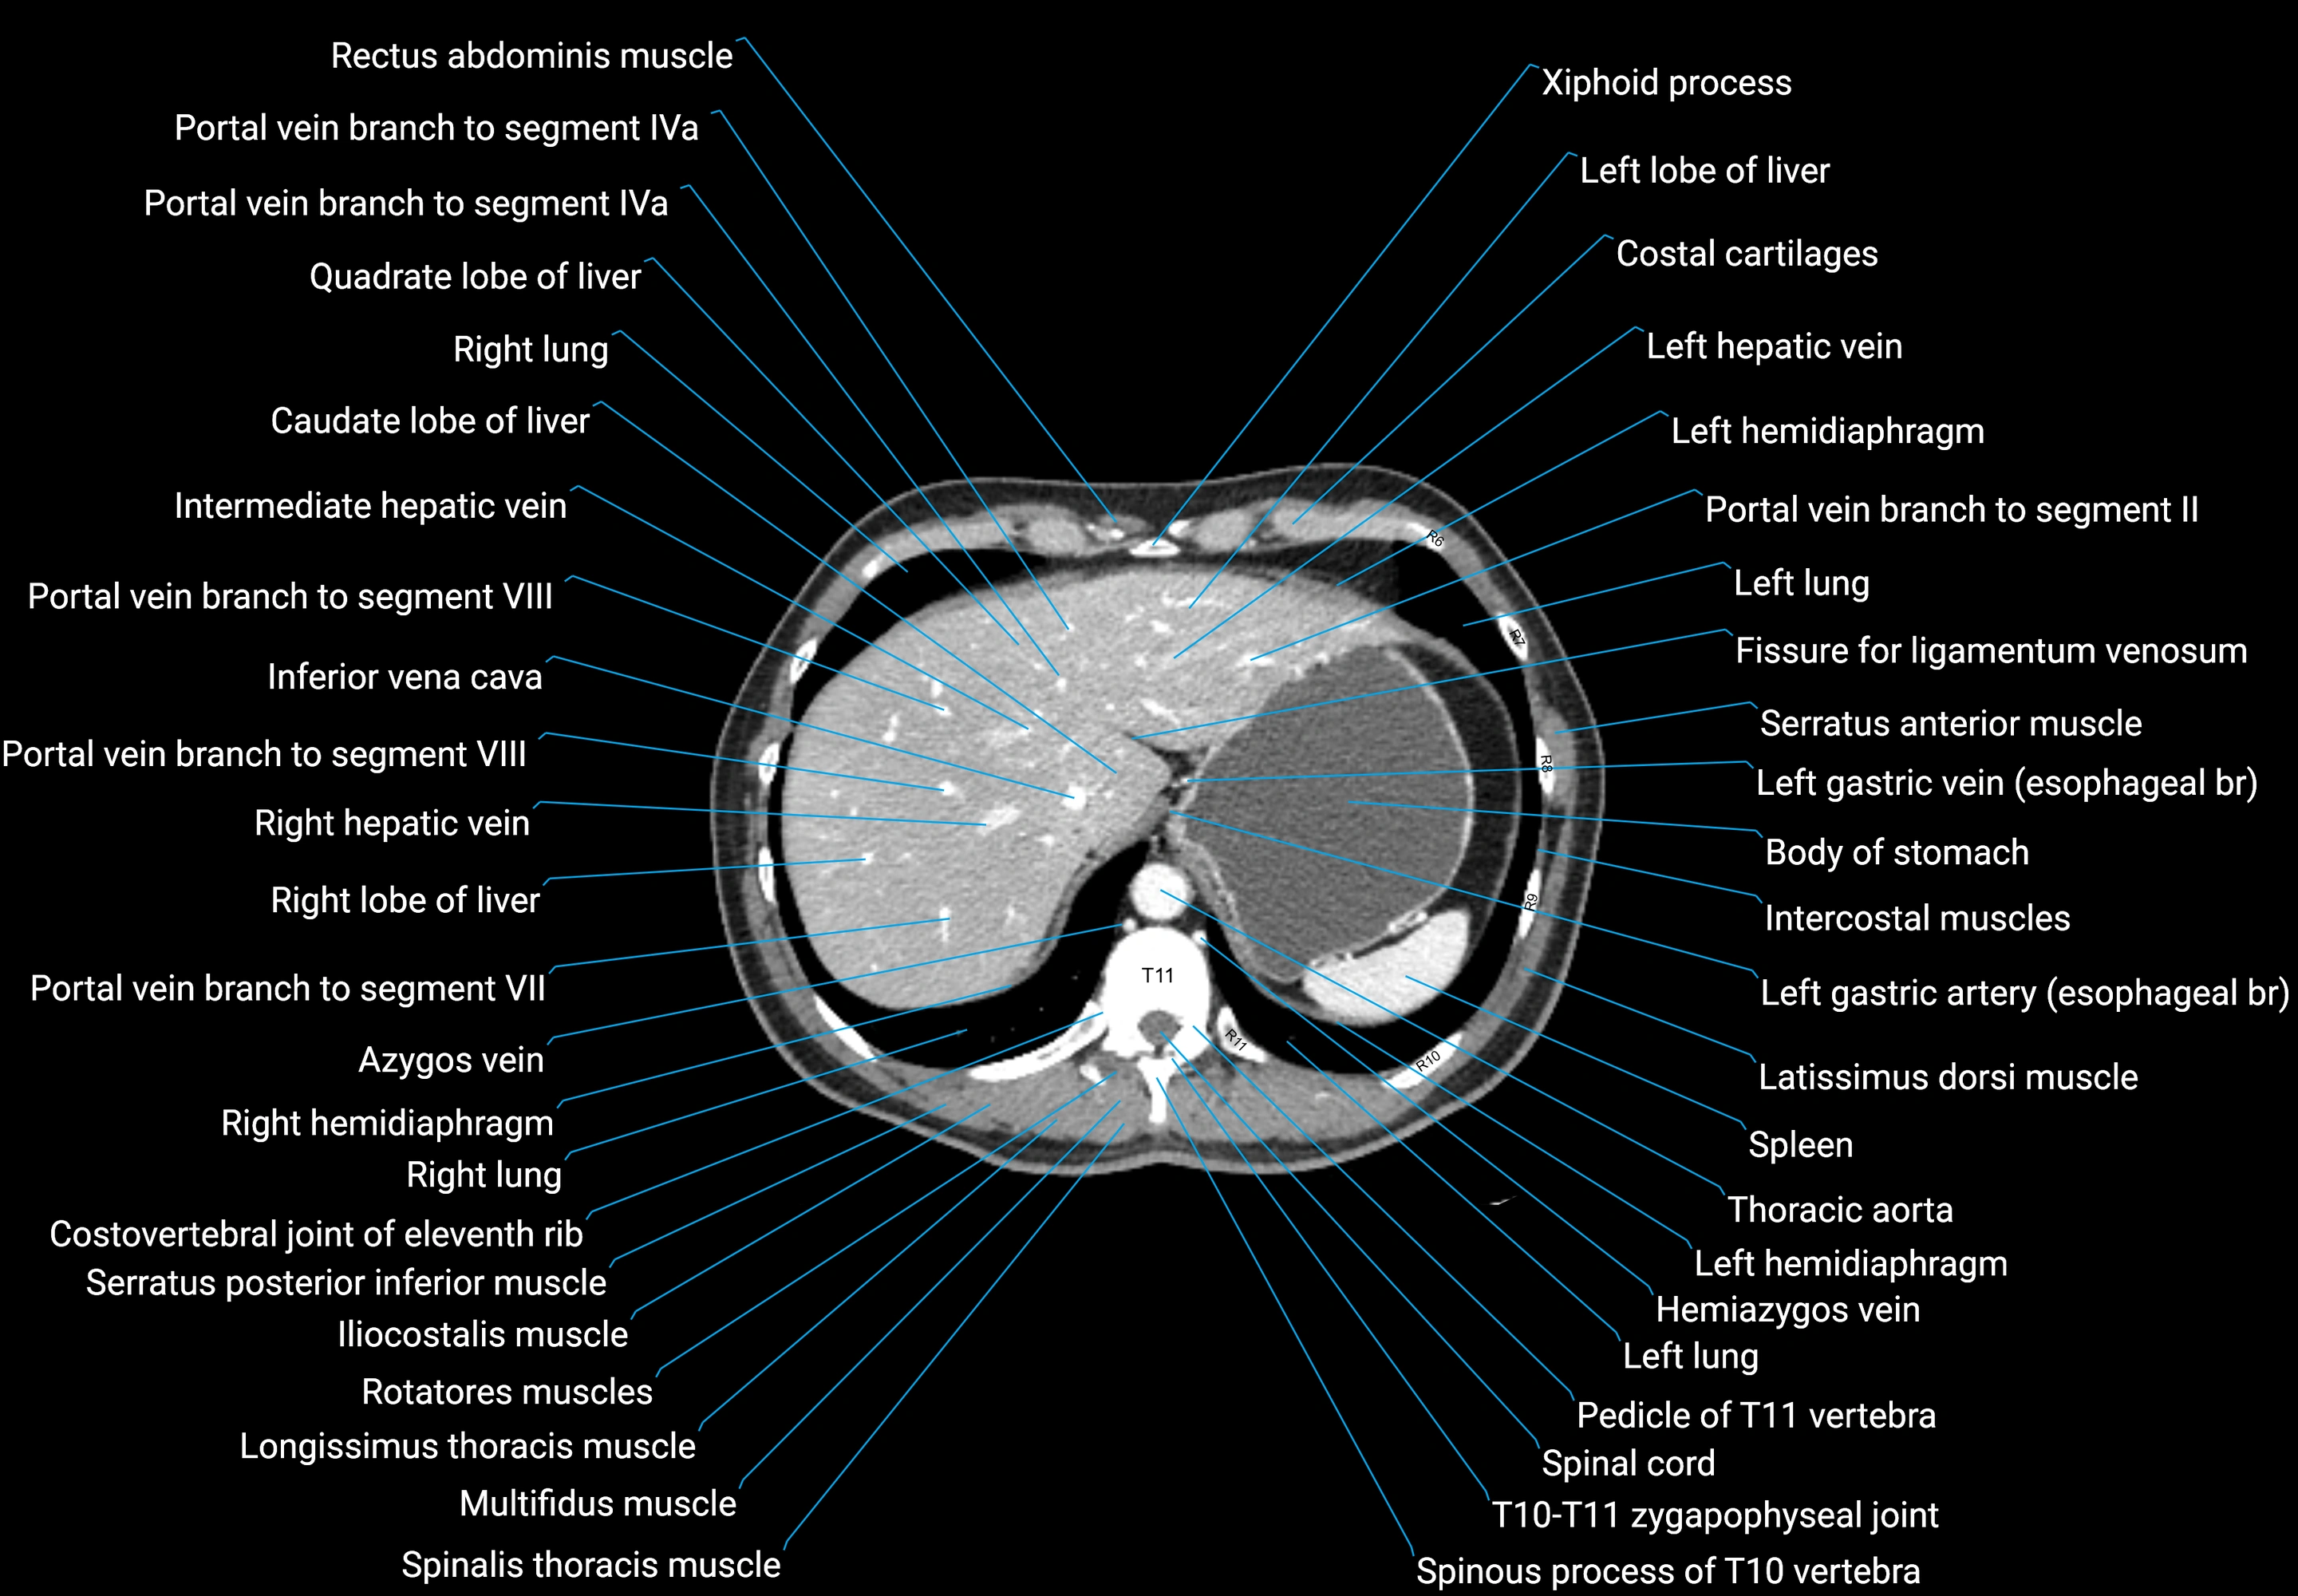

CT images